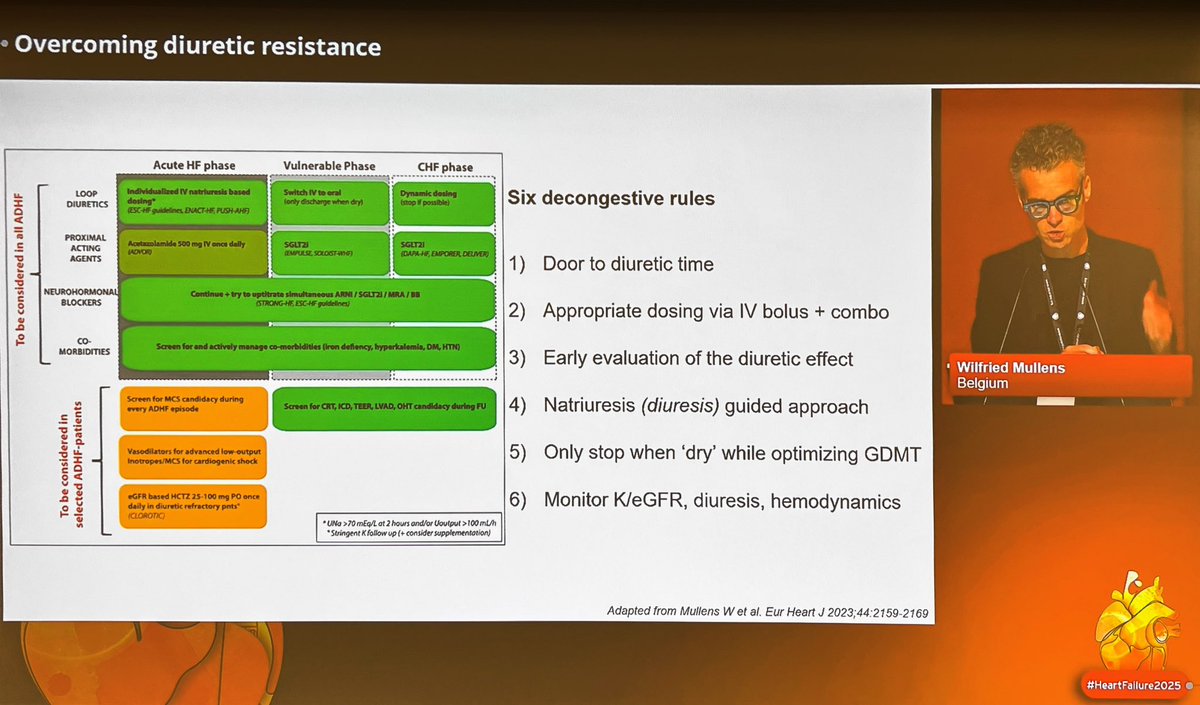

Fantastic six decongestive rules💦 by Wilfried Mullens 1️⃣Door to diuretic time 2️⃣Appropriate dosing via IV bolus + combo 3️⃣Early evaluation of the diuretic effect 4️⃣Natriuresis guided approach 5️⃣Only stop when 'dry' while optimizing GDMT 6️⃣Monitor K/eGFR, diuresis, hemodynamics